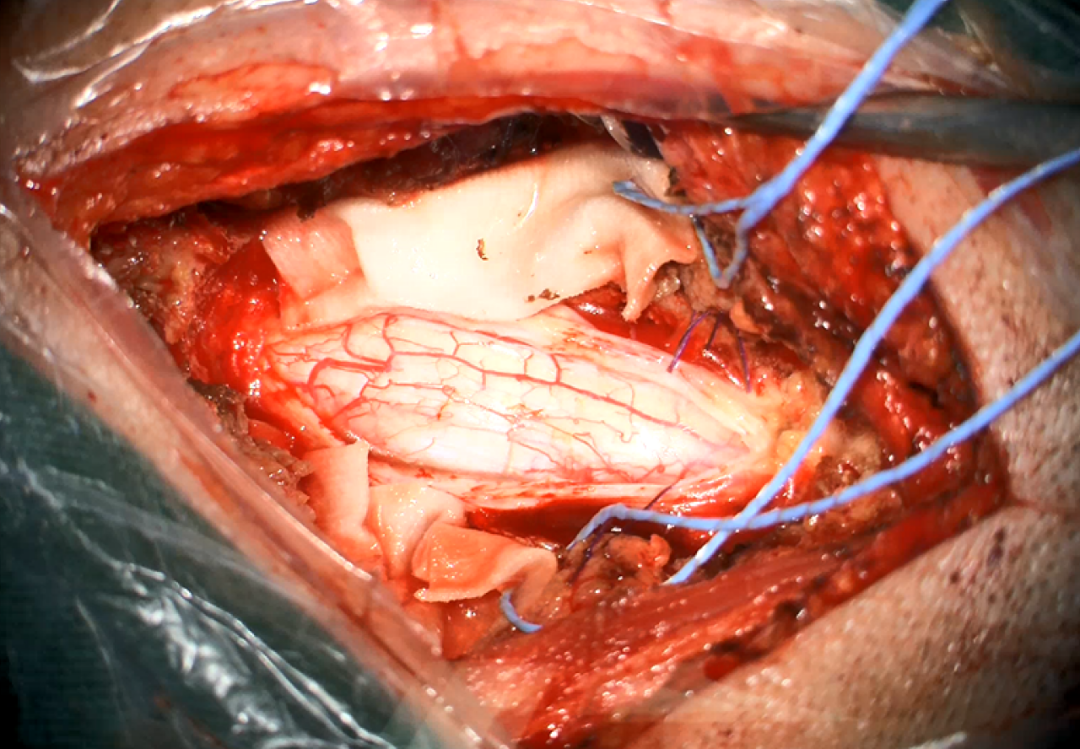

术中图片:

图4. 确定肿瘤边界并根据吸引器所在位置实时自动对焦

图5. 根据导航沿着肿瘤边界切开脑膜,并用黄荧光进一步确定肿瘤边界

图6. 分离肿瘤与脑组织及引流静脉的黏连,最终完整切除肿瘤